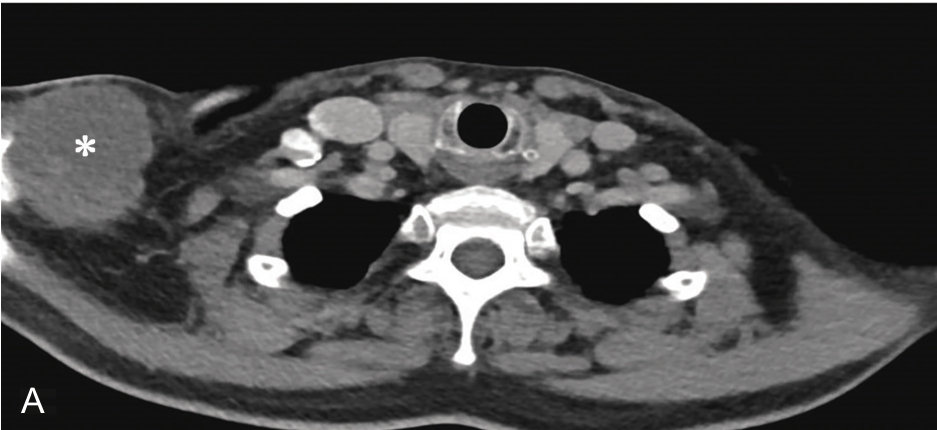

▲ 图2-1-12 超声引导下右侧肩关节周围滑膜囊肿穿刺治疗

A~B.患者肩关节MRI,星号及测量键:滑膜囊肿